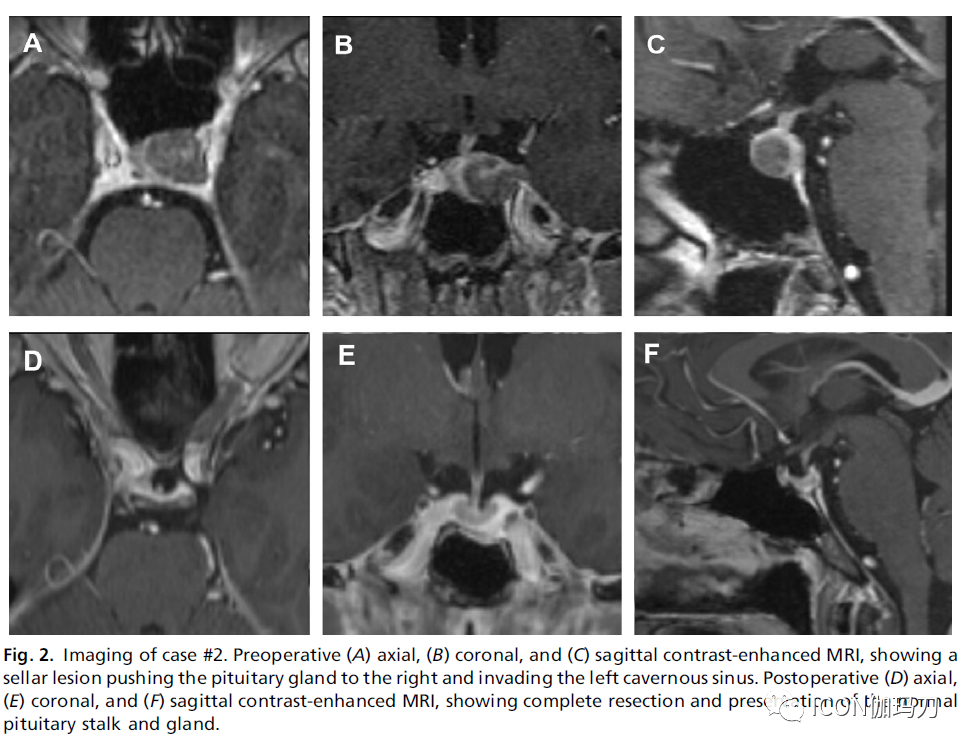

检查:除了已经治疗的小脑转移瘤,脑部MRI显示T2WI上病变与垂体等信号,垂体腺的其余部分没有强化,位于左侧鞍区(见图2A-C)。内分泌检查是正常的。PET扫描显示鞍区及锁骨上、纵隔、肺门及胃及肝脏区有高代谢性病变。

图2.病例2影像学检查。术前(A)轴位、(B)冠状位、(C)矢状位增强MRI显示鞍区病灶将垂体推向右侧并侵袭左侧海绵窦。术后(D)轴位、(E)冠状位和(F)矢状位增强MRI显示完整切除肿瘤并保存正常的垂体柄和腺体。

处理:决定对他的垂体病灶进行手术,以便有标本作明确诊断。拟经鼻内镜经蝶入路。达到术后MRI随访证实肿瘤完全切除(图2D-F)。